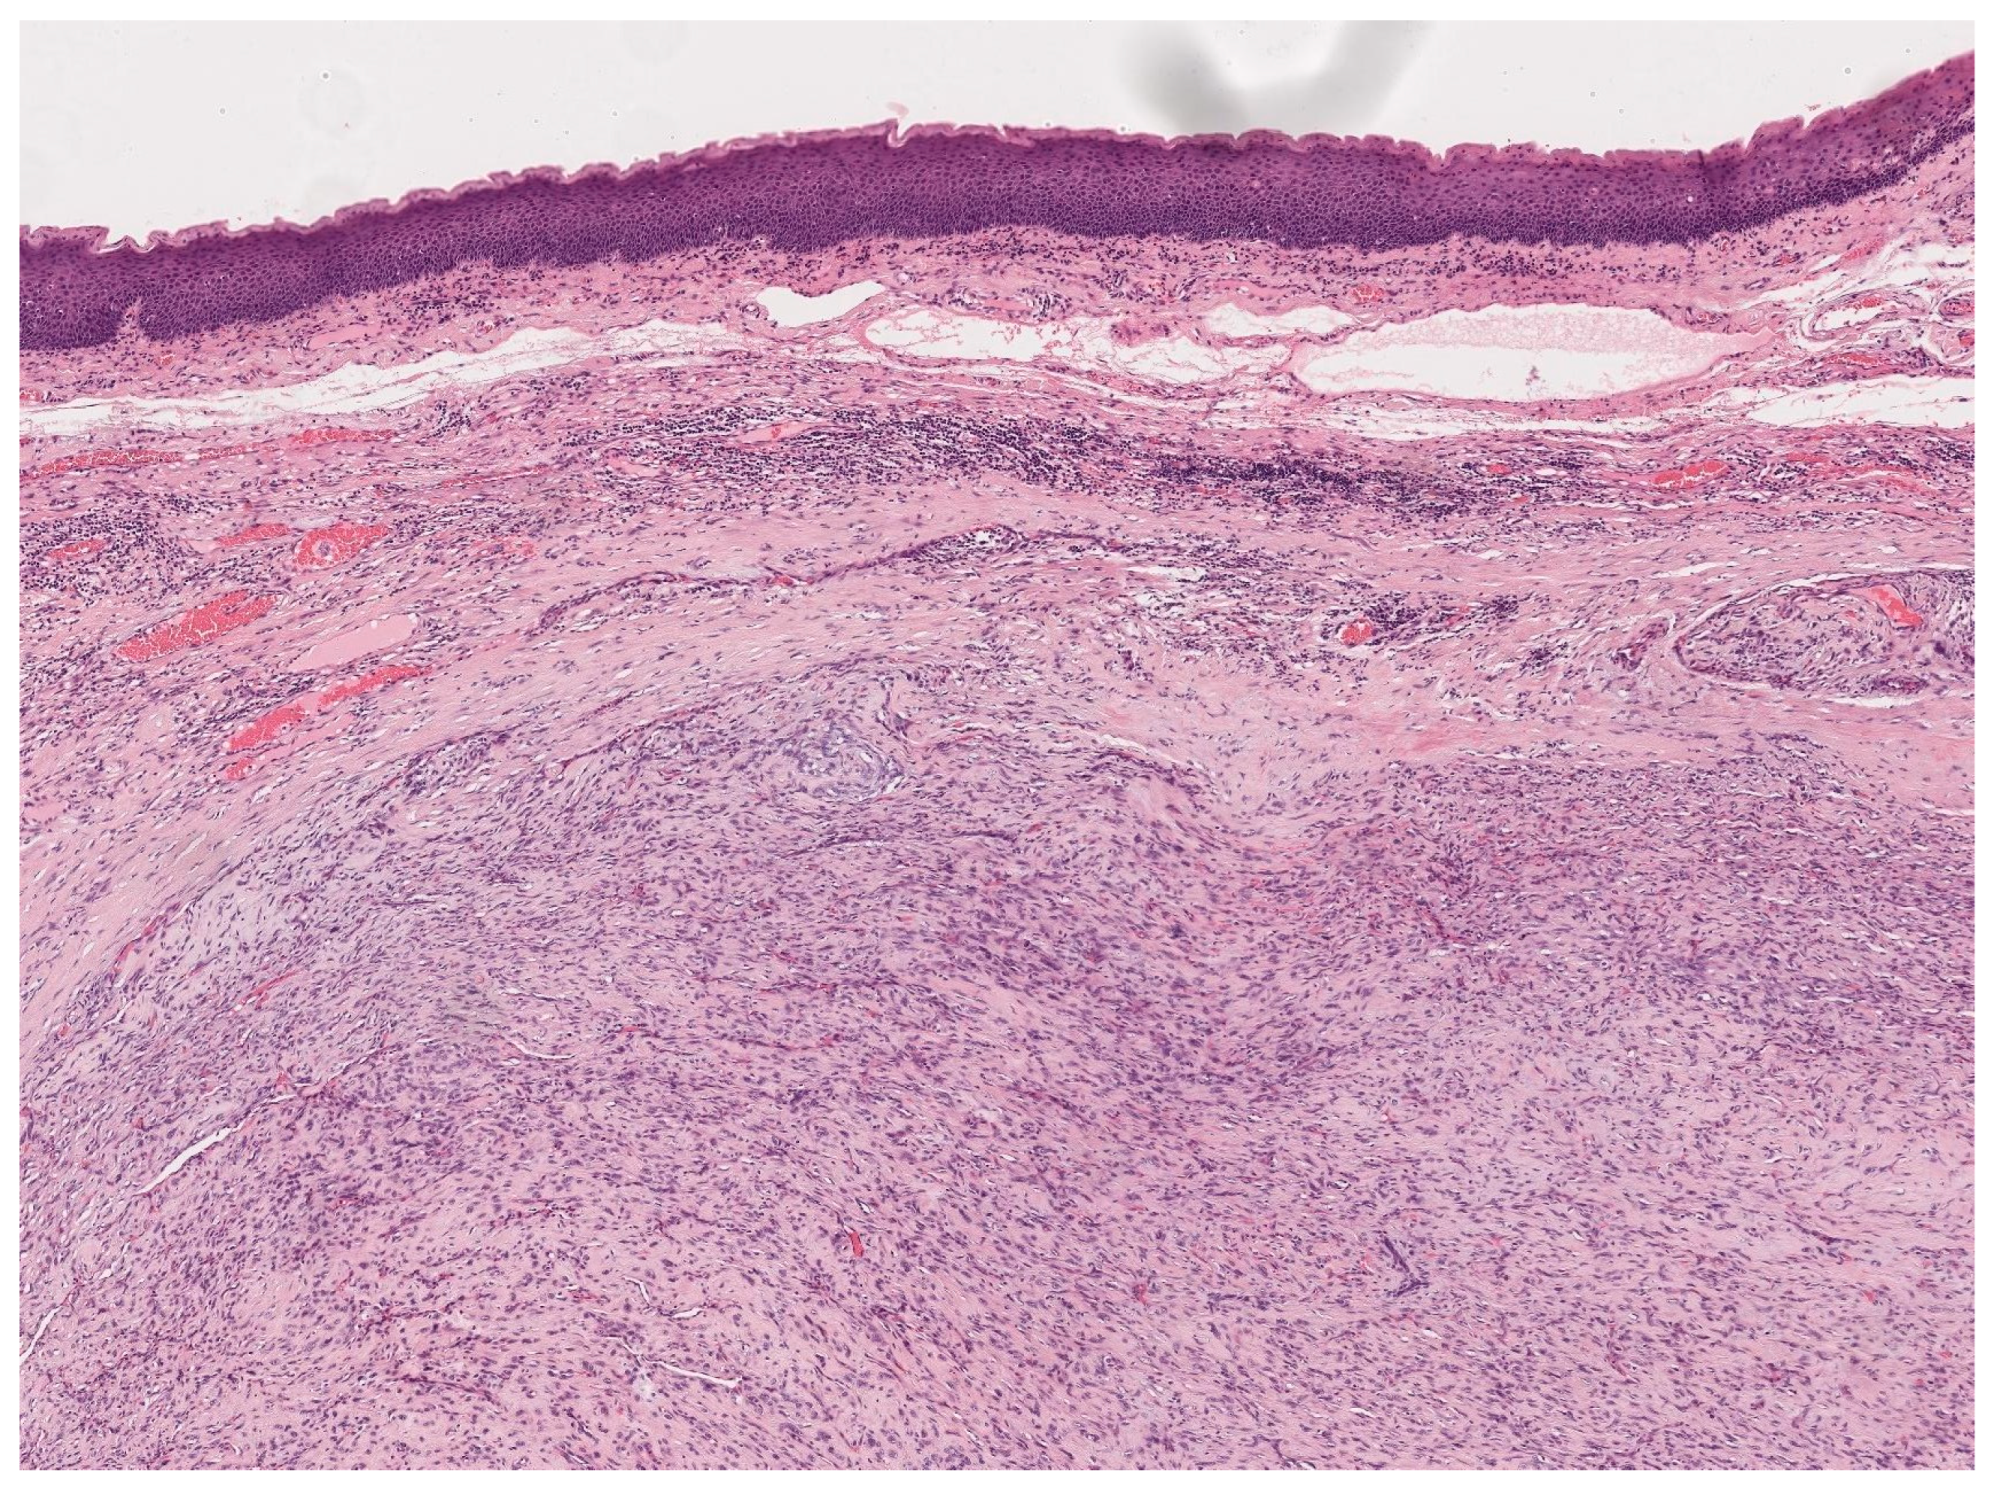

3.3. Spindle-Cell Carcinoma

- Thompson, L.D.; Wieneke, J.A.; Miettinen, M.; Heffner, D.K. Spindle cell (sarcomatoid) carcinomas of the larynx: A clinicopathologic study of 187 cases. Am. J. Surg. Pathol. 2002, 26, 153–170. [Google Scholar] [CrossRef] [PubMed]